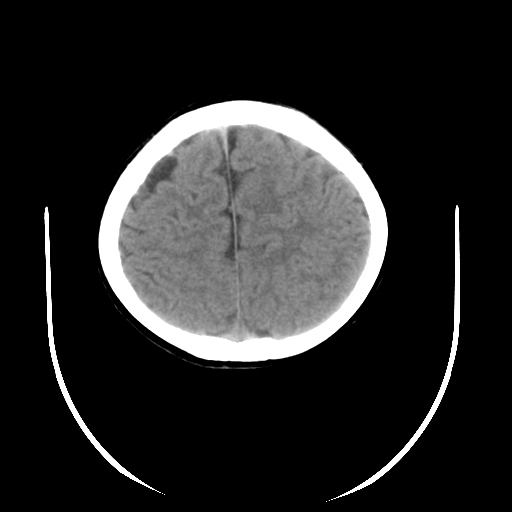

女,6岁,头痛、呕吐一天。